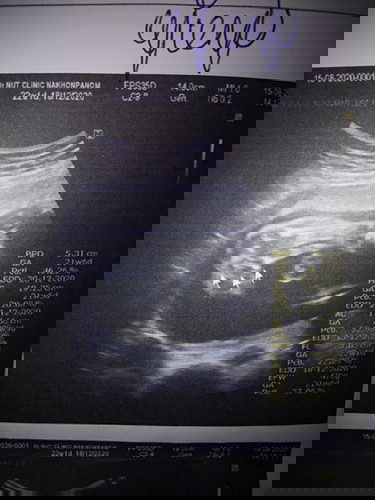

อัตตราซาวด์หมอบอกว่าผู้หญิงแบบนี้จะชัวร์หรือป่าวคะ

ชัวร์ค่ะ